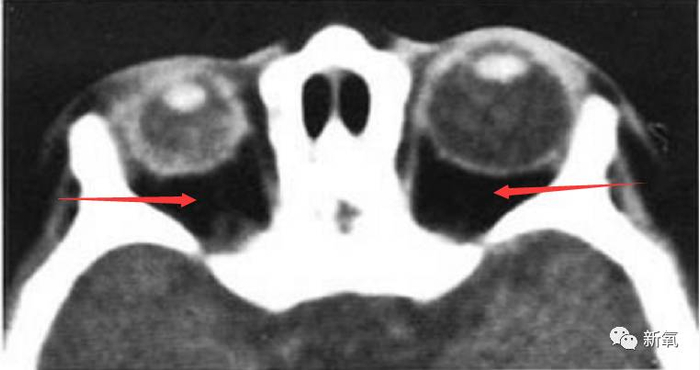

上面的没看明白的话看下面这张图,轴性的是整个变长,屈光的是红箭头所指的中心点变长,最终的结果都是显得眼睛更加突出。

感受一下同一个人的眼球变化。